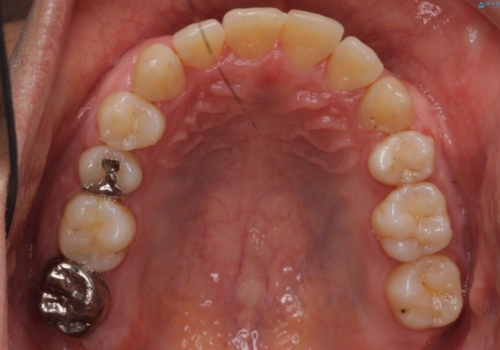

受け口 絶対に顎の手術はしたくない

- 受け口を主訴に来院。

下あごが大きく、顎の手術を含めた矯正をおすすめしましたが、手術は怖いので絶対にしたくないとのことでした。

歯並びのみを治す矯正は難しく、長期にわたる治療になるとご説明しました。

かみしめもあり、骨も固く、歯根も長いためなかなか歯が動かず、患者様も治療する側も忍耐を要する長期戦となりました。